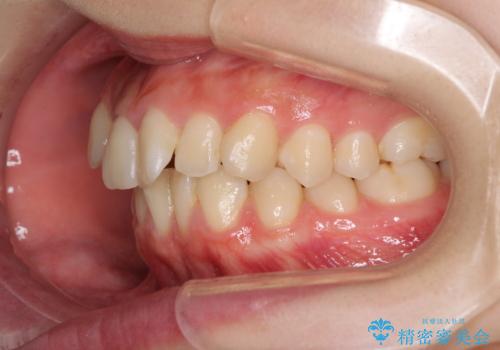

- 前歯のデコボコを気にして来院された患者様です。

本人は気づいていませんでしたが、下顎前歯が2本欠損しており、上下の歯列がアンバランスとなりデコボコになっていました。

上下のバランスを取るため、上顎左右第一小臼歯2本を抜歯し、ワイヤー矯正を行うこととしました。